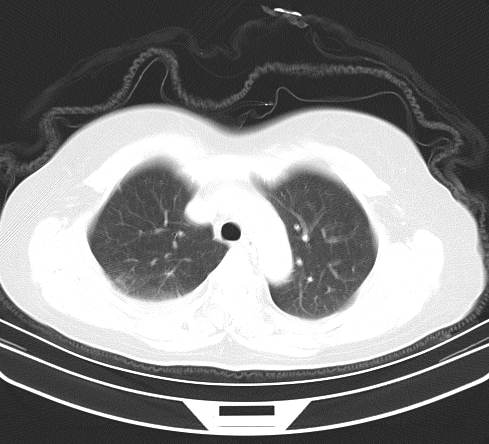

以下是引用余辉在2009-2-19 20:10:00的发言:[br]多考虑急性感染性病变,右中叶尚可见多枚小斑片状影,多为化脓性肺炎,双侧胸腔积液

以下是引用随光逐影在2009-2-19 20:33:00的发言:[br]1)考虑右肺炎症;建议抗炎治疗后复查。2)双侧胸腔积液(以右侧为甚)。

以下是引用花凤凰在2009-2-19 20:46:00的发言:[br]病人有发热,胸痛急性起病,主要病变位于右肺中叶外侧段,呈楔行改变,位于外带胸膜下,考虑为肺梗塞可能!!!!!!!!!!!!!!!!!!!!!!!!!!!!!!!!!!!